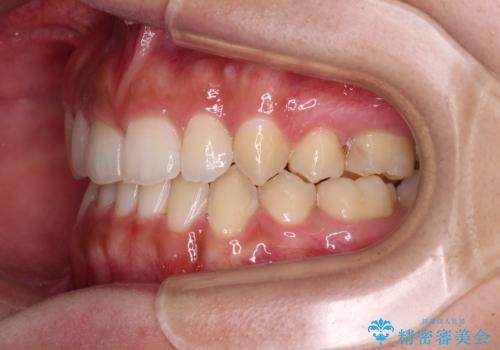

著しい八重歯が気になる インビザラインでの矯正治療

- 顕著な八重歯が気になるとのことで来院された患者様です。

インビザラインでの治療を希望されましたが、インビザライン単独では困難と判断されたため、補助装置や一部ワイヤー装置を用いて行うこととしました。

叢生が強いため、上下左右第一小臼歯4本を抜歯することとしました。